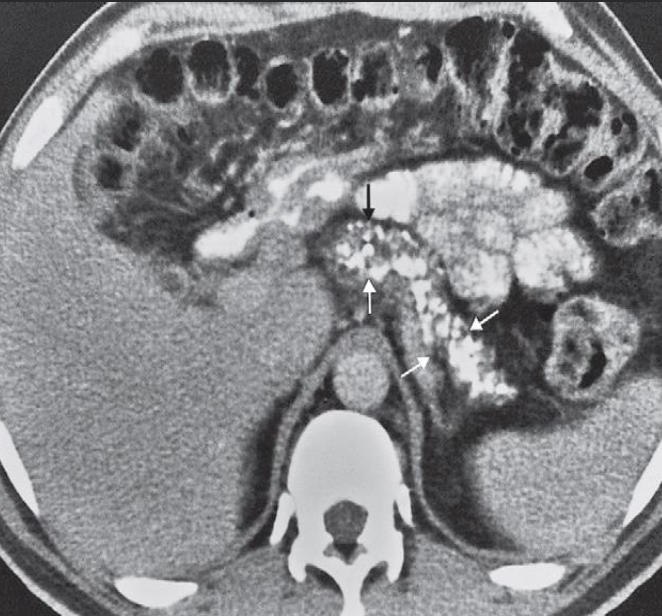

A. Describe the abnormality marked by arrows in the given image.

- CT scan showing numerous

- small areas of calcification

- within the pancreas (arrows).

B. What is the most probable diagnosis in the given image. Chronic pancreatitis